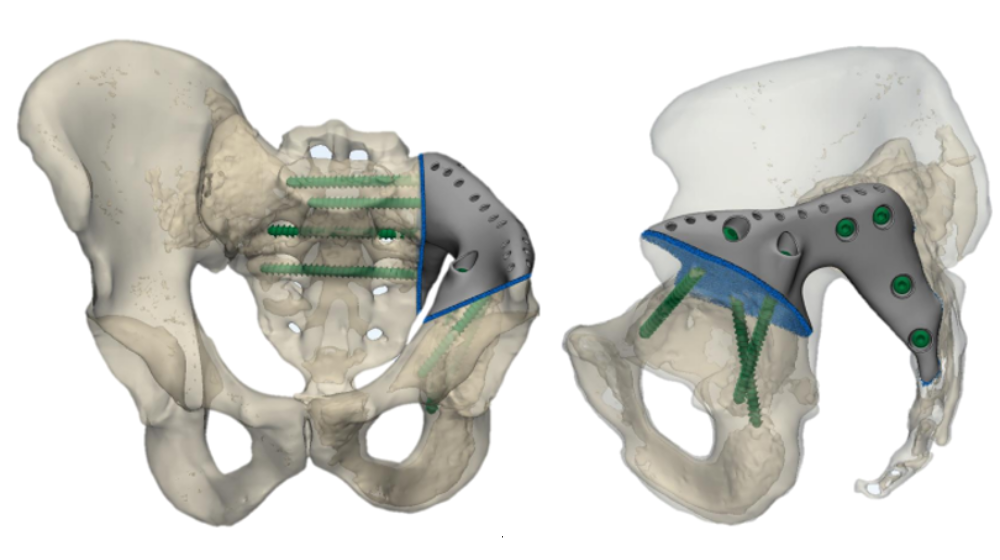

Замена таз сустава

Замена таз сустава 113 фотографий